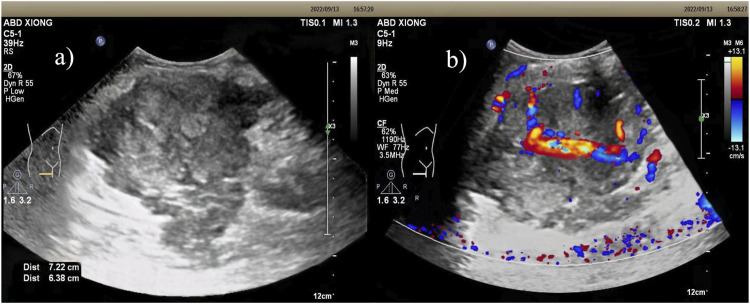

Synovial sarcoma (SS) is a rare and malignant mesenchymal neoplasm. We report a case of a 16-year-old Chinese female diagnosed with biphasic synovial sarcoma. The imaging features, surgical procedures and pathological results of the lesion were described in detail. Additionally, we conducted a review of the literature on synovial sarcoma of the thigh over the past 2 decades, identifying a total of 25 relevant case reports and summarizing the characteristics of these cases. Synovial sarcoma has a high degree of malignancy, with a high recurrence and metastasis rate, and a 5-year survival rate of 36%-76% and a 10-year survival rate of 20%-63%, so early detection of the lesion and preoperative differential diagnosis are of paramount importance in the treatment of patients.